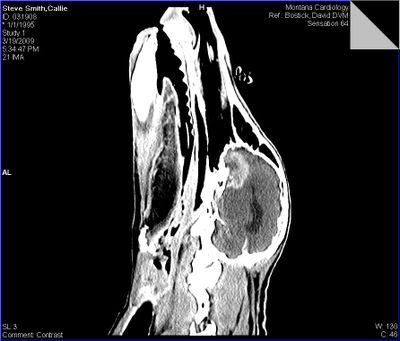

We found out yesterday evening that blind Callie does indeed have a brain tumor. A large one. In this vertical view of her head from the CAT scan image, it's the bright glowing thing at the base of her brain at the front end. (The dark area in the center of her brain is the cerebral fluid.)

Dave said that her tumor is most likely a meningioma, which are generally benign — and if you can shrink it down with radiation, you relieve the pressure inside the brain that is triggering the seizures. He said that oncologists generally have a high success rate treating these kinds of brain tumors with radiation.

To see a larger version of the scan, click on the image.